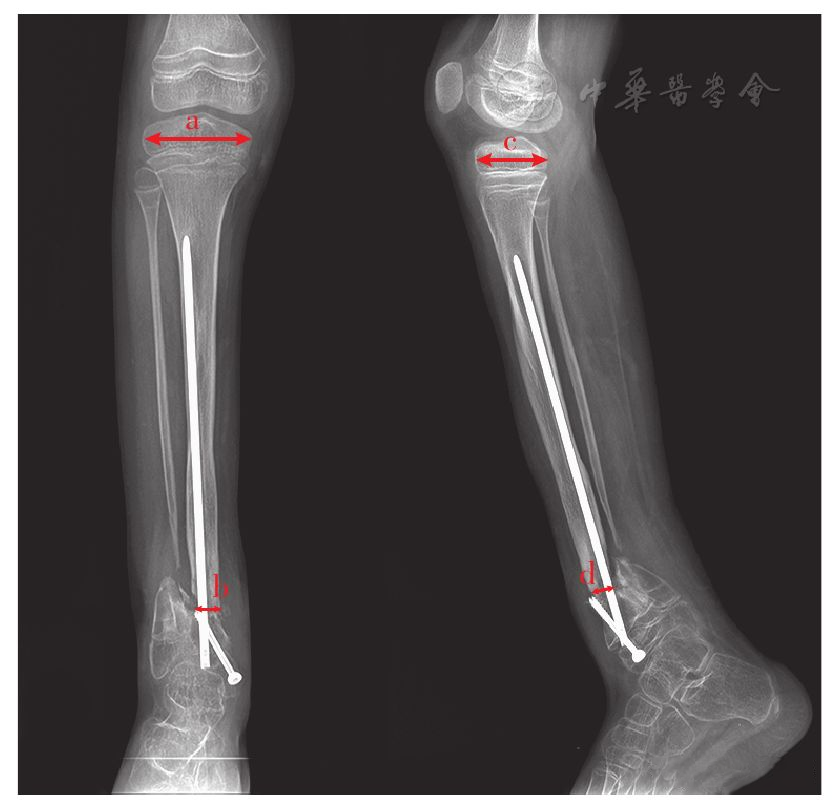

根据Choi等[26]提供的测量方法,假关节愈合处横截面积相对比即为假关节再骨折部位在正、侧位X线片上最狭窄处横径乘积与同侧胫骨近端干骺端骺板在正位及侧位片横径乘积的比值(图1)。对于在随访截止时间内未发生再骨折的病例,假关节愈合处横截面积相对比的测量需根据再骨折病例的中位无骨折生存时间来确定,具体测量方法同再骨折病例。

图1 假关节愈合处横截面积相对比的X线计算方法。a为正位片胫骨近端骺板横径,b为正位片再骨折部位胫骨横径,c为侧位片胫骨近端骺板横径,d为侧位片再骨折部位胫骨横径。(b×d)/(a×c)即假关节愈合处横截面积相对比